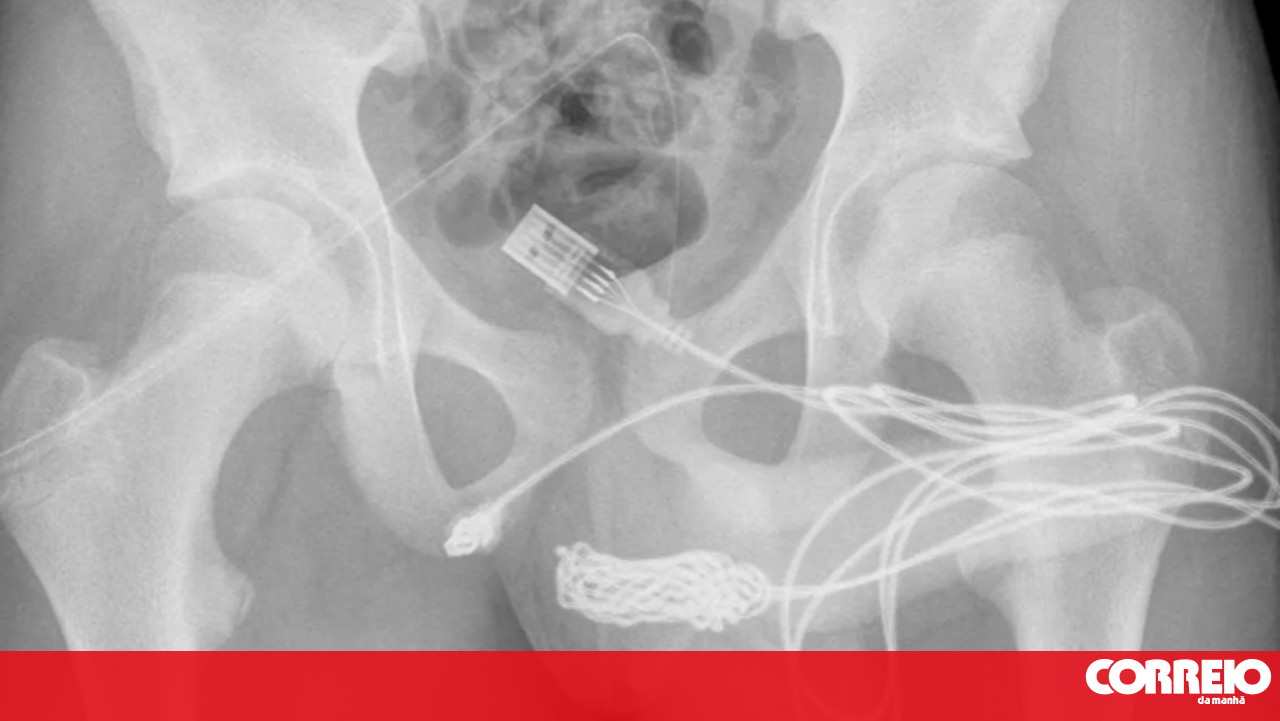

Um adolescente britânico acabou numa mesa de operações depois de inserir um cabo USB no pénis... porque queria medir o tamanho do órgão.

Após ser examinado, os médicos constataram que o jovem de 15 anos tinha um cabo dentro do órgão genital.

O adolescente, envergonhado, disse aos médicos que tinha inserido o cabo na uretra para medir o comprimento do pénis "por curiosidade sexual" e que tinha tentado retirá-lo, mas não conseguiu.